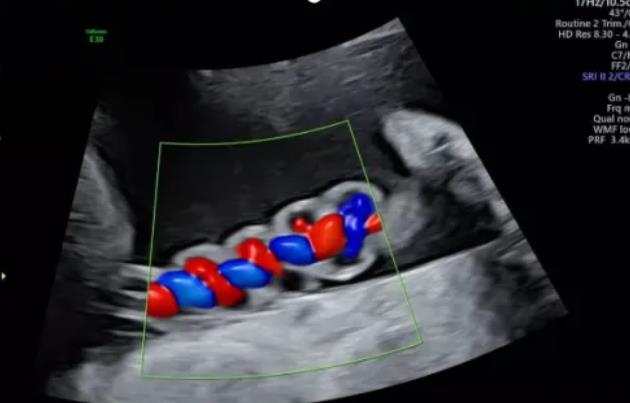

漯河市中醫(yī)院健康科普:超聲檢查之臍帶螺旋

臍帶螺旋指數(shù)(umblical coiling index UCI)指每1cm臍帶螺旋的周數(shù),等于臍帶的完全扭轉(zhuǎn)數(shù)÷臍帶長度(cm);為臍血管扭轉(zhuǎn)的診斷提出了量化標準,它能反映螺旋的周數(shù),更重要的是能夠反映螺旋的疏密度,是簡單、客觀、量化臍帶血管螺旋的指標。

正常范圍及意義:正常情況下,臍血管生理性扭轉(zhuǎn)約6~11螺旋,即臍帶約5cm形成1個完全的螺旋圈,UCI<0.07考慮為螺旋過松;UCI﹥0.36考慮為螺旋過緊。理論上講過松和過緊均會影響胎兒發(fā)育。

聲像圖特征:臍動脈表現(xiàn)為過度螺旋,臍血管變細,縱切面呈“麻花狀”,橫切面呈“鼠眼狀”;

聲像圖特征:胎兒臍帶縱切面示血管呈平行排列,螺旋稀少,彩色多普勒血流成像示臍帶血管內(nèi)充滿的紅藍血流呈平行排列,麻花狀螺旋消失。